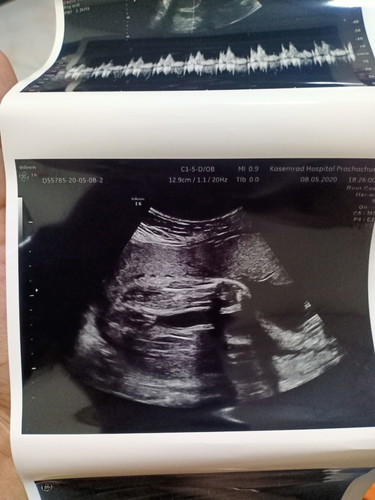

แม่ๆค่ะ แบบนี้คือได้ลูกสาวชัวใช่ไหมค่ะ แม่ๆดูออกไหมค่ะ คุณหมอบอกได้ลูกสาวค่ะ

มาเป็นกลีบเลยแม่ ลูกสาวค่ะ